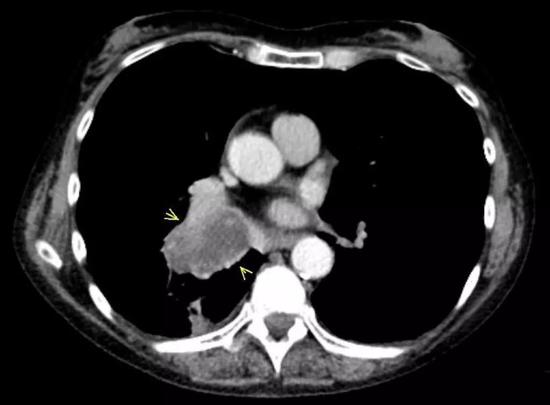

现在高维医学成像已经能在宏观上把肿瘤看得明明白白。但是科学家的野心不止于此,他们希望能用这双火眼金睛,直接看到肿瘤组织的细胞和分子层面上去,彻底认清肿瘤的本质。

也就是说,Deutsch博士团队直接想从患者肿瘤组织的CT影像上看出肿瘤里面的免疫细胞水平,然后预测患者对免疫治疗响应的程度。

他们选取了一个叫MOSCATO的队列[10],这个队列的135名患者都患有晚期实体瘤,并且他们的CT图像以及肿瘤组织的转录组测序数据都有保存。其中,这些转录组测序数据可以用来计算肿瘤中CD8细胞的数量。

研究者们又用了一个叫TCGA队列[11,12],包括119名患者,这些患者也都有CT图像和转录组测序数据。用算法计算这队列的CD8细胞数量,与对应转录组数据计算的数量一致,表明算法是可靠的。